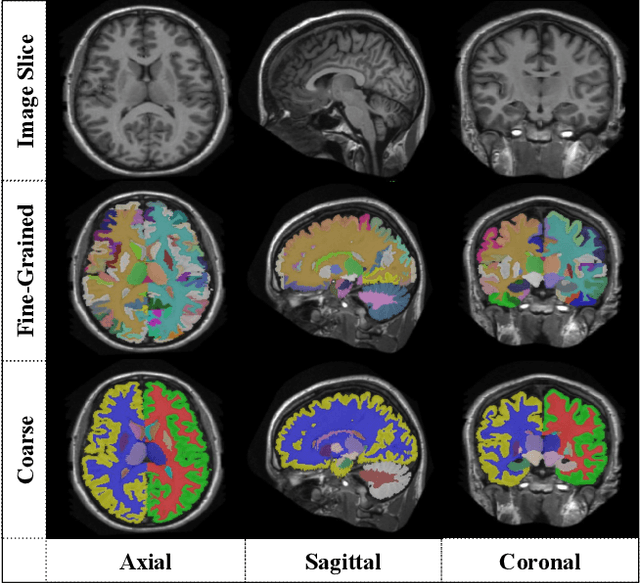

Abstract:Segmentation of brain structures from magnetic resonance (MR) scans plays an important role in the quantification of brain morphology. Since 3D deep learning models suffer from high computational cost, 2D deep learning methods are favored for their computational efficiency. However, existing 2D deep learning methods are not equipped to effectively capture 3D spatial contextual information that is needed to achieve accurate brain structure segmentation. In order to overcome this limitation, we develop an Anatomical Context-Encoding Network (ACEnet) to incorporate 3D spatial and anatomical contexts in 2D convolutional neural networks (CNNs) for efficient and accurate segmentation of brain structures from MR scans, consisting of 1) an anatomical context encoding module to incorporate anatomical information in 2D CNNs, 2) a spatial context encoding module to integrate 3D image information in 2D CNNs, and 3) a skull stripping module to guide 2D CNNs to attend to the brain. Extensive experiments on three benchmark datasets have demonstrated that our method outperforms state-of-the-art alternative methods for brain structure segmentation in terms of both computational efficiency and segmentation accuracy.

Abstract:Automatic segmentation of fine-grained brain structures remains a challenging task. Current segmentation methods mainly utilize 2D and 3D deep neural networks. The 2D networks take image slices as input to produce coarse segmentation in less processing time, whereas the 3D networks take the whole image volumes to generated fine-detailed segmentation with more computational burden. In order to obtain accurate fine-grained segmentation efficiently, in this paper, we propose an end-to-end Feature-Fused Context-Encoding Network for brain structure segmentation from MR (magnetic resonance) images. Our model is implemented based on a 2D convolutional backbone, which integrates a 2D encoding module to acquire planar image features and a spatial encoding module to extract spatial context information. A global context encoding module is further introduced to capture global context semantics from the fused 2D encoding and spatial features. The proposed network aims to fully leverage the global anatomical prior knowledge learned from context semantics, which is represented by a structure-aware attention factor to recalibrate the outputs of the network. In this way, the network is guaranteed to be aware of the class-dependent feature maps to facilitate the segmentation. We evaluate our model on 2012 Brain Multi-Atlas Labelling Challenge dataset for 134 fine-grained structure segmentation. Besides, we validate our network on 27 coarse structure segmentation tasks. Experimental results have demonstrated that our model can achieve improved performance compared with the state-of-the-art approaches.